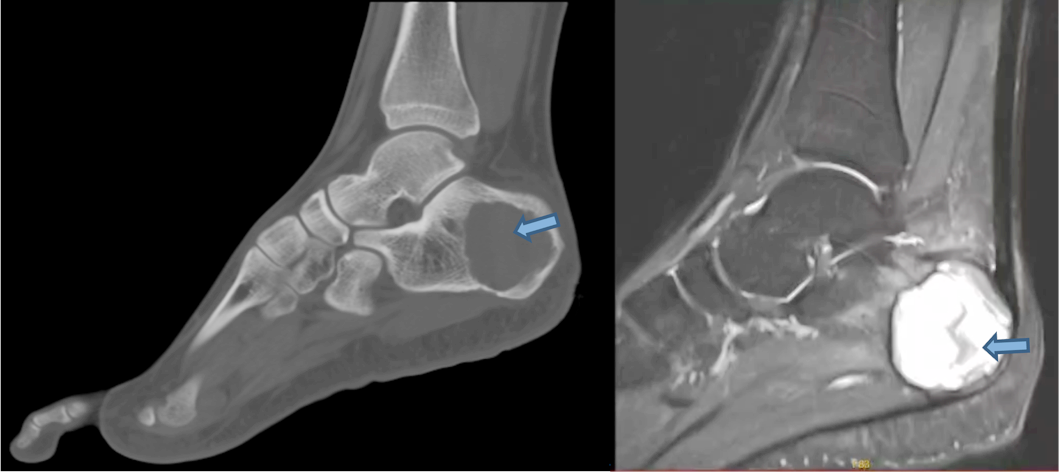

近日,20岁的李先生因左足跟活动后反复疼痛半年余后到我院就诊,关节外科和运动医学科医疗团队为李先生进行诊疗,诊断为左跟骨动脉瘤样骨囊肿,并成功为该患者进行了左跟骨病灶微波灭活+病损切刮+骨水泥重建术,术后患者症状明显缓解并功能恢复良好。

▲左跟骨动脉瘤样骨囊肿,侵袭范围超过跟骨1/2

李先生曾多次外院就诊但症状依旧没有缓解,经多方打听,遂来到我院就诊。关节外科和运动医学科曾红生主任带领的骨肿瘤诊疗团队经全面的专科检查后发现,李先生左跟骨病灶为动脉瘤样骨囊肿,不排除为骨巨细胞瘤合并动脉瘤样骨囊肿,难点在于病灶范围较大(约4×4cm),已累及超过1/2跟骨体积,如何保证在彻夜灭活肿瘤的前提下重建跟骨功能是手术难点。针对患者的复杂情况,省医派驻专家、关节外科和运动医学科副主任黄文汉主持了全科术前讨论,手术团队认为本次手术的风险及难点在于跟骨瘤腔较大且病灶隐匿,如何保证囊肿病灶均得到处理是关键步骤;跟骨为人体负重重要器官,如何重建其功能且实现长期预后良好是一大难点。经过全科细致的讨论,决定为患者施行左跟骨病灶微波灭活+病损切刮+骨水泥人工骨复合体重建术+创面负压吸引术。

动脉瘤样骨囊肿好发于20岁以下青少年,男女无显著差异,好发于长骨干骺端和椎体附件,临床症状一般较轻,主要为局部肿胀疼痛,呈隐匿性发病。病变的诊断要点是病灶内可见液-液平面,这是因血细胞和血浆的分离和沉淀所致,在T2WI上,液面上层为高信号,下层为低信号,T1WI上则相反,上层为低信号,下层为偏高信号。手术治疗是本病的主要治疗方式,传统的单纯刮除、刮除植骨复发率可高达20%-30%,给患者带来沉重负担。微波消融具有灭活囊腔彻底、效率高(瞬时灭活肿瘤细胞)等特点,可最大程度保留骨量,是治疗该疾病的最佳手段。